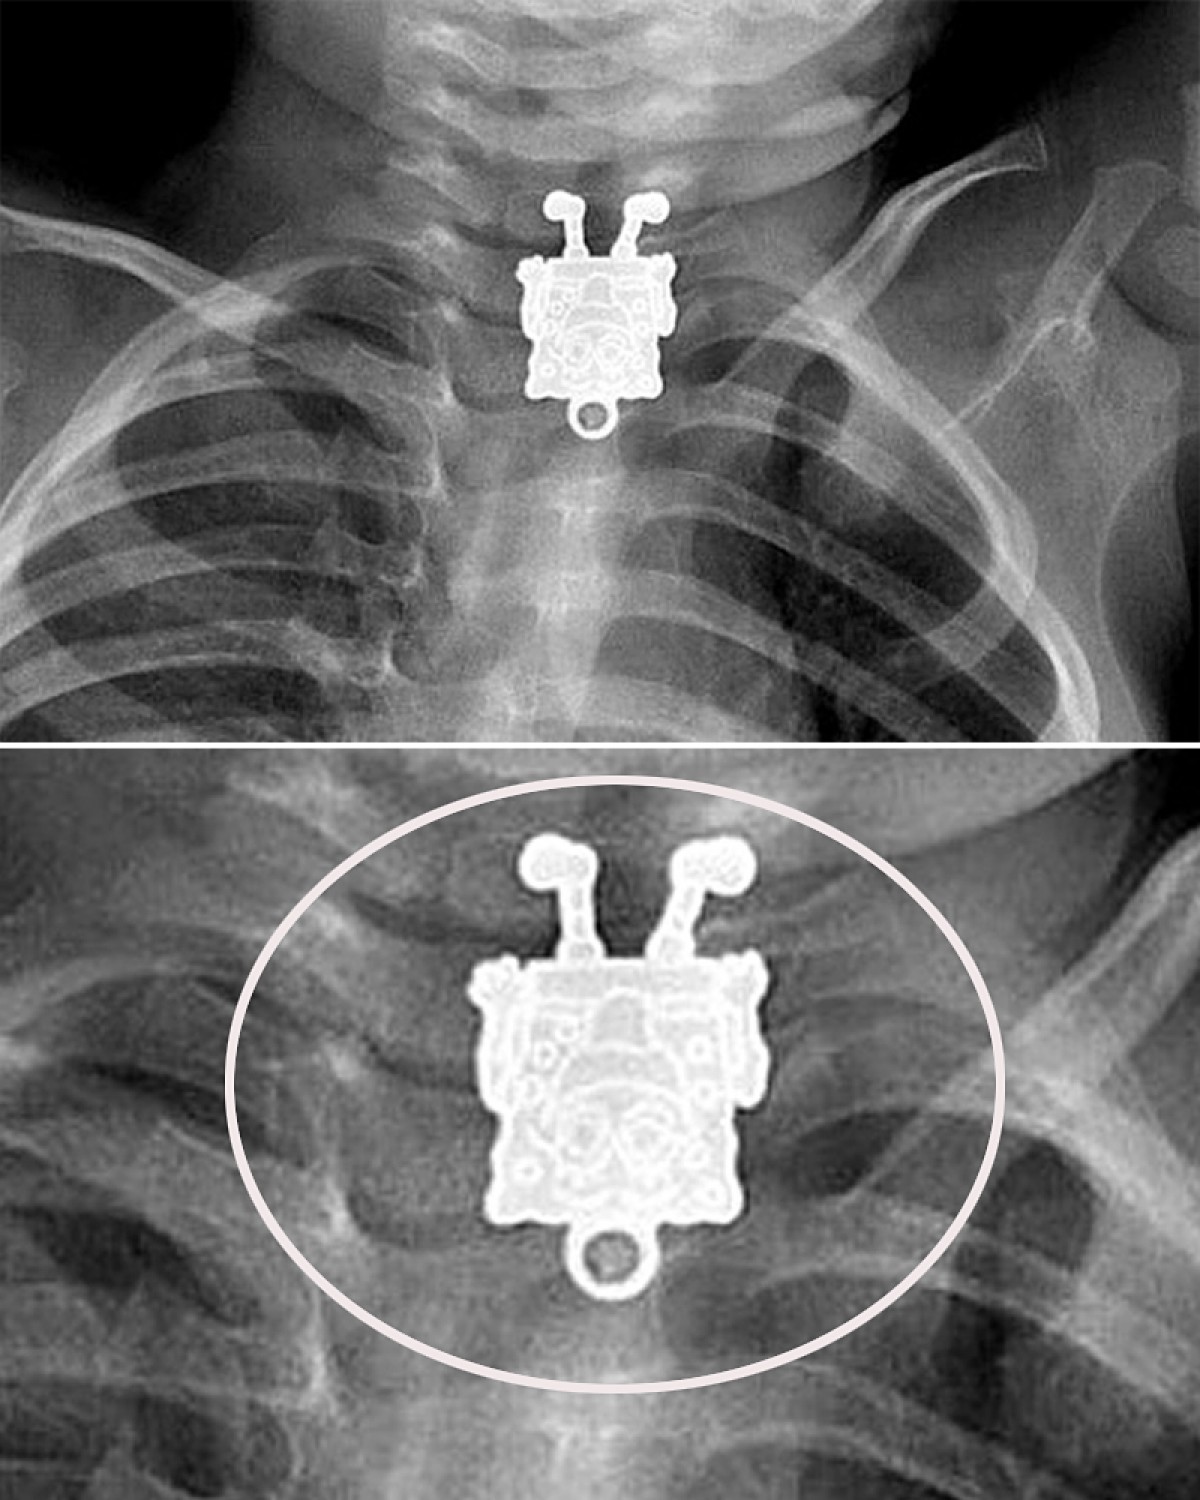

何でも口に入れたがる子供の誤飲は後を絶たない。サウジアラビアのとある病院に1歳4ヵ月の子供がやってきた時も医師は「ピン止めやアクセサリーを飲み込んだ」と踏んでレントゲンを撮影。しかし、予想外の異物とその“笑顔”に病院は騒然となったという。

「あまりにはっきりと映っていたので、つい声をあげてしまいました。手足から、そばかすに至るまで全て見えているでしょう」と話すのは、撮影を行ったレントゲン技師。写真は、異例のレントゲン写真を医師たちが公表するサイト「Radiopaedia(ラディオペディア)」にて投稿された。

サイト運営者は「数多くの変わった写真を見てきましたが、これは特に素晴らしい!」と興奮気味にコメント。なお、このペンダントは医師の手により無事に摘出されたそうだ。